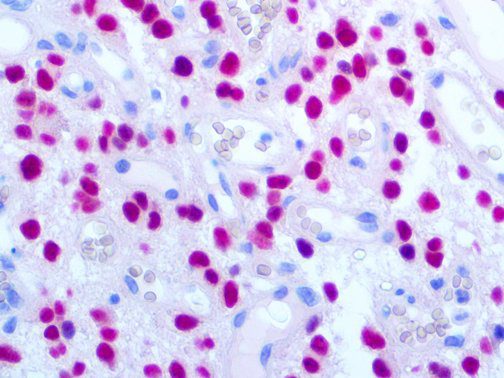

It is the ICU physician who is most likely to witness one of the deadliest manifestations of the abnormal immunological response, the cytokine storm syndrome (CSS). This response is also referred to by some as the cytokine release syndrome (CRS). CSS is characterized by continuous activation and expansion of macrophage and lymphocyte populations, which secrete large amounts of cytokines, causing the cytokine storm. This massive cytokine release is akin to hemophagocytic lymphohistiocytosis (HLH) disease, a syndrome characterized by initial unchecked and persistent activation of cytotoxic T lymphocytes and NK cells.

Clinical and laboratory manifestations of HLH include fever, enlarged liver and/or spleen, neurologic dysfunction, coagulopathy, liver dysfunction, cytopenias (i.e., low levels of erythrocytes, leukocytes, and/or platelets), hypertriglyceridemia, hyperferritinemia, hemophagocytosis, and eventually diminished NK cell activity as the immune system becomes progressively paralyzed. HLH can be familial (primary HLH) or secondary to another disease process (sHLH), such as rheumatic disease, in which it is referred to as macrophage activation syndrome (MAS, characterized by elevated ferritin).